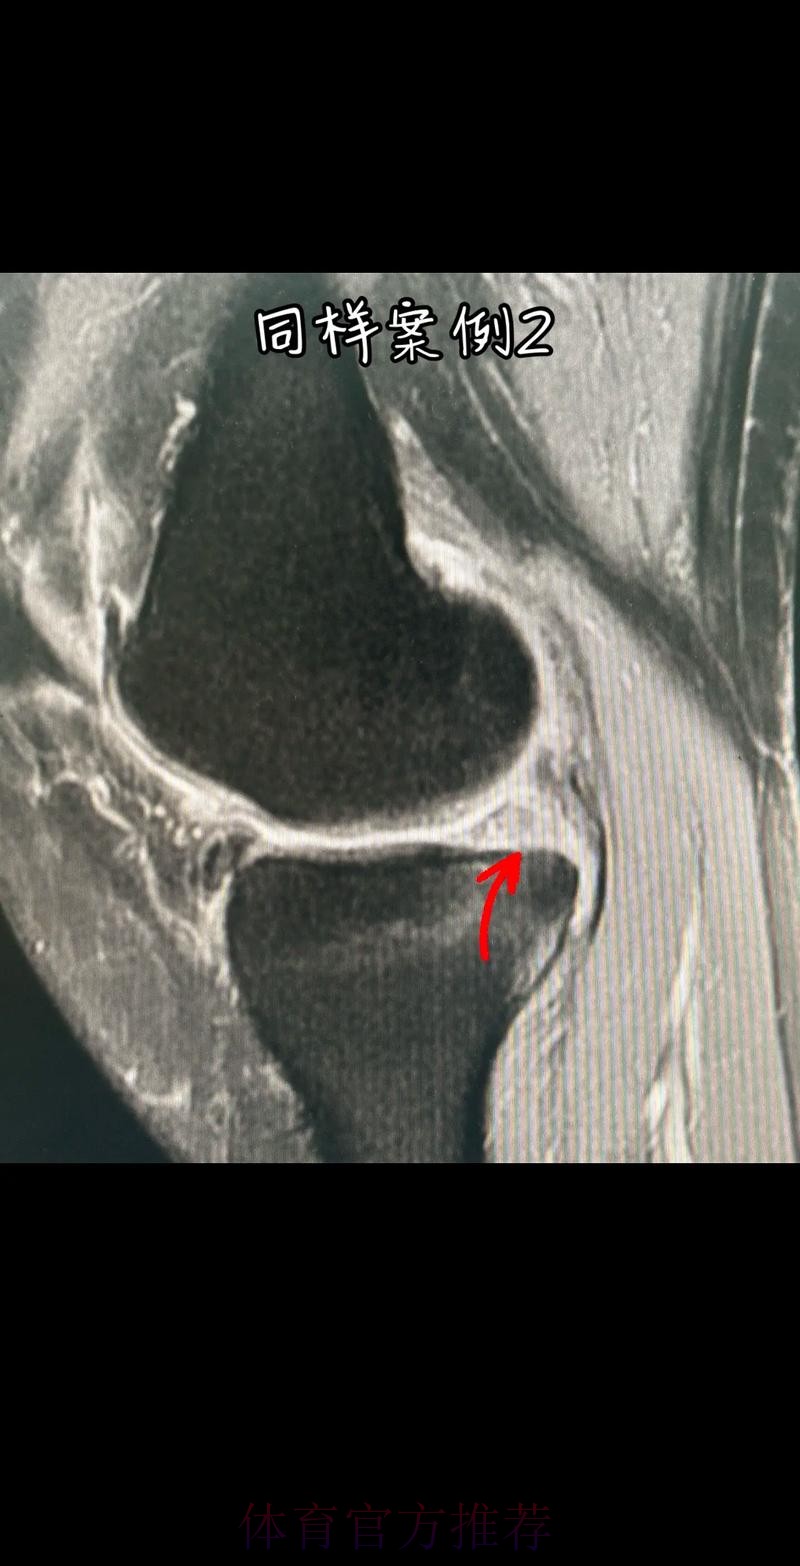

这条“官方 阿拉巴左膝内侧半月板撕裂 预计伤缺6-8周”的声明一出 不只是伤病通告那么简单 它背后牵动的是皇马后防体系的重塑 奥地利国家队备战计划的调整 以及一名顶级后卫职业生涯中一次关键的健康考验 对于已经习惯在高强度赛程中同时承担俱乐部与国家队重任的阿拉巴来说 这次伤病既是一次身体的警报 也是一次心理与战术层面的巨大挑战

在现代足球中 像阿拉巴这样能胜任中卫 左后卫 甚至后腰的多面手几乎是教练心中最理想的拼图 他不仅是后场的防守屏障 更是从后场发起进攻的节拍器 因此 当“左膝内侧半月板撕裂 伤缺6-8周”这样的诊断从官方口中给出时 对球队来说 就等同于在关键路段突然失去一块核心路基 球迷最直观的担忧是 皇马在这段时间是否还能保持防线稳定 奥地利是否在国际比赛日期间陷入被动 而对阿拉巴本人而言 这则官方消息意味着一个不得不按下暂停键的阶段 他需要重新面对恢复训练 康复计划 以及未来的竞技状态

阿拉巴在皇马的定位从来不只是“中后卫”这么简单 他可以在三中卫体系中担任左中卫 也可以在四后卫体系中出现在左后卫甚至拖后组织者的位置 在很多场次中 他会频繁前插 参与推进和组织 这意味着他在身体对抗 启动速度 横向移动和急停变向上的负荷都极高 半月板本身就处在运动生物力学的核心位置 当一名球员同时承担高强度防守和大量持球推进任务时 半月板承受的剪切力和压缩力都会显著增加 这也是为什么像阿拉巴这样“全能型”球员 更容易在高密度赛程中出现膝关节相关损伤

从医学角度看 半月板是膝关节内一块呈“C”形的软骨结构 其作用是缓冲冲击 稳定膝关节 并帮助分散压力 “左膝内侧半月板撕裂”通常说明在一次急停 旋转 或对抗中 半月板受到了超过其承受极限的力导致结构损伤 这类伤病常见于足球 篮球等需要频繁变向和对抗的项目 对于职业球员而言 半月板损伤严重程度不一 但共同点是都会影响支撑发力 跳跃以及变向时的稳定性 而官方给出的“预计伤缺6-8周”这个时间区间 往往对应的是中度损伤或通过微创手术加积极康复能够较快回归的情况 也意味着暂时没有出现必须长时间休战的最坏结果

表面上看 6-8周只是一个时间区间 但对顶级球队的赛程来说 这段时间可能包含多场联赛 甚至关键杯赛淘汰轮 相当于缺席一个赛季中最密集的一段周期 需要强调的是 这个“预计”并不是绝对数字 它取决于撕裂的位置 大小 修复方式 以及球员个体的恢复能力 有时若采取保守治疗 球员在6周时即可参与部分训练 但要达到比赛要求则可能接近8周甚至稍长 此外 精英运动员的康复不仅仅是伤口愈合 还包括力量恢复 协调重建 和心理自信的回归 阿拉巴要在有限时间内完成从“伤病患者”到“可靠首发”的角色转换 这一过程复杂程度远远超出一纸通告所能呈现